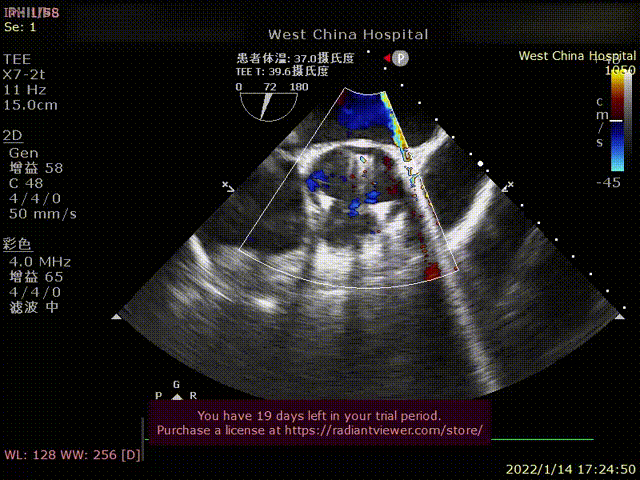

患者为70岁女性,因“心悸、胸闷16余年,反复1年,加重1天 “主诉入院。术前超声提示左心增大,左室为著,LVDD 71mm,LVEF 41%,主动脉瓣中重度反流。术后即刻主动脉瓣大量反流消失,LVDD 62mm,左心较术前明显缩小。

术前超声影像

术后超声1

术后超声2